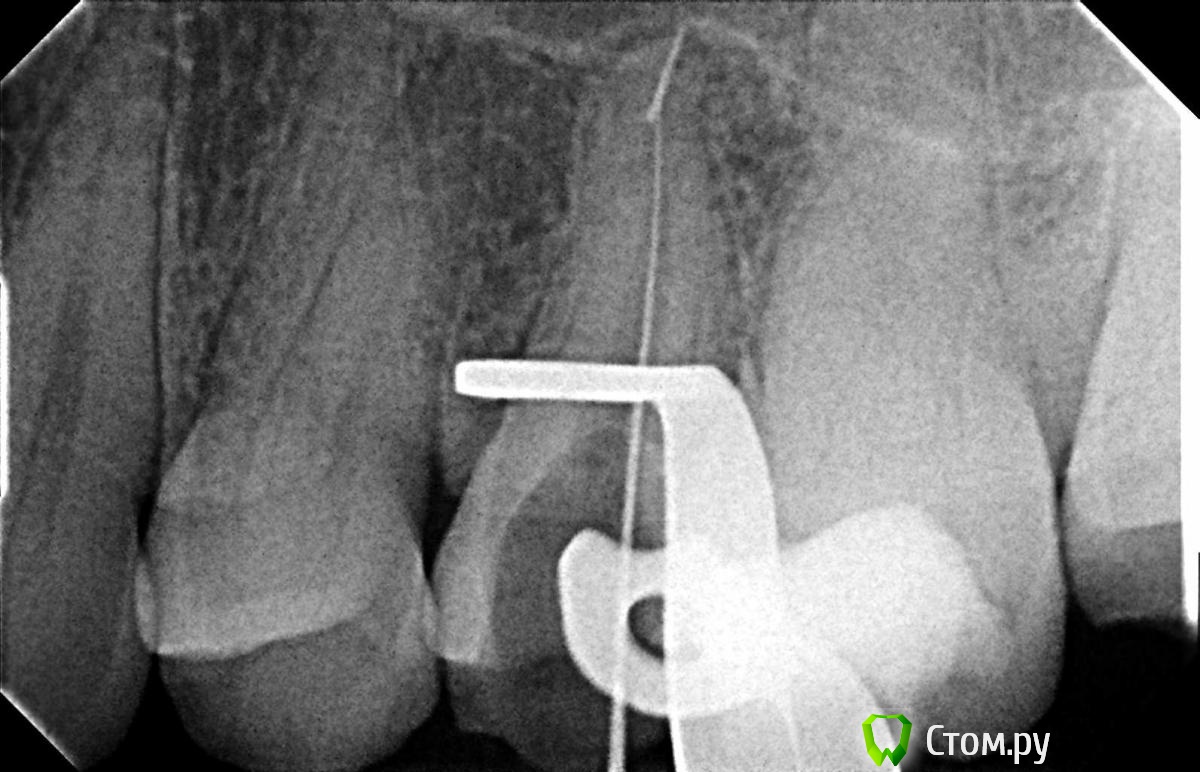

Hans85 Опубликовано 8 января, 2014 Поделиться Опубликовано 8 января, 2014 Только зарегистрировался на форуме,хотелось бы познакомится с коллегами.для начала выкладываю небольшой кейс с названием "Почти мини".Направлен пациент прошло 6 месяцев после фиксации композитной вкладки,заболел.Эндо без рук (только контроль проходимости 10 К-file)Rece+ProFile,пломбирование волна.Всем здравствуйте.P.S Сан Саныч привет)). 12 Ссылка на комментарий

Hans85 Опубликовано 8 января, 2014 Автор Поделиться Опубликовано 8 января, 2014 Кстати насчет ретрита-случай из разряда ну пожалуйста доктор или спасение рядовой 6ки. 8 Ссылка на комментарий

Hans85 Опубликовано 8 января, 2014 Автор Поделиться Опубликовано 8 января, 2014 НУ еще чуток доступа может кому будет интересноПациент - геморная кариозная полость по дистальной поверхности 47,точка сообщения с полостью зуба обнаружилась,традиционный доступ уничтожил бы зуб,пришлось хитрить. 11 Ссылка на комментарий